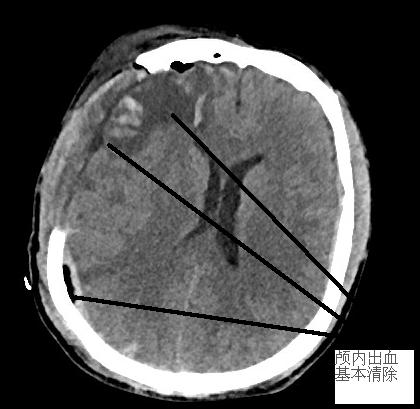

手術(shù)后復(fù)查CT,患者顱內(nèi)血腫對腦組織壓迫已解除,中線恢復(fù),環(huán)池清楚,顱內(nèi)壓下降,患者意識狀態(tài)逐漸清醒,轉(zhuǎn)病房作進(jìn)一步后續(xù)術(shù)后及康復(fù)治療。

手術(shù)前后對比